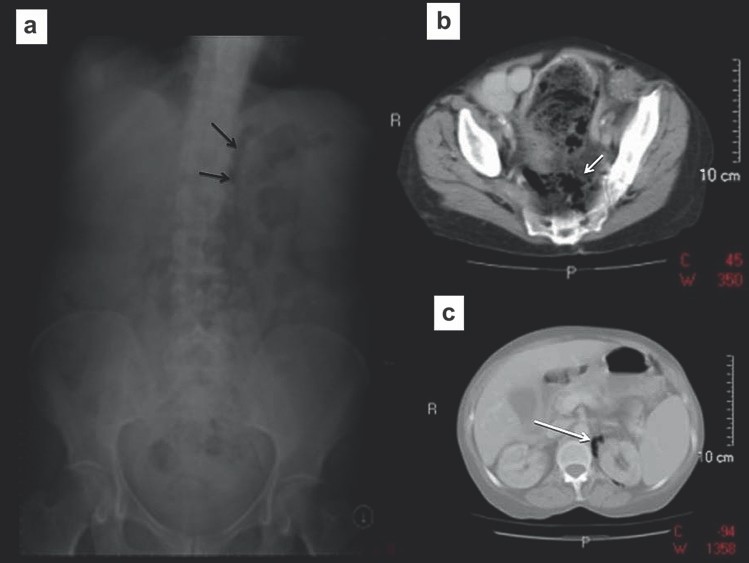

Nguyên nhân dẫn tới tắc ruột non, đặc biệt là thoát vị, đôi khi có thể nhận ra trên phim X quang và nên được tìm kiếm một các hệ thống trong tắc ruột. Điều này yêu cầu phim X quang bụng phải bao phủ cả vùng bẹn vì đó là vị trí hay thoát vị gây tắc ruột nhất. Thoát vị bịt hoặc thoát vị rốn đôi khi tạo nên các mẫu hình khí gợi ý trên phim X quang, do đó chụp cắt lớp vi tính kéo xuống mức thấp hơn để đánh giá chi tiết (Hình 2). Tắc ruột do sỏi mật và các khối ổ bụng gây tắc ruột đôi khi cũng có thể được phát hiện.

Hình 2. Tắc ruột non do thoát vị nghẹt lỗ bịt. (a) Nhiều quai ruột non giãn. Lưu ý có một ít khí dưới dây chằng bẹn ở lỗ bẹn phải (b,c) Chụp CT cho thấy một quai ruột ở giữa cơ bịt trong và cơ bịt ngoài, xác định thoát vị bịt bên phải gây tắc ruột.

Xoắn xảy ra khi đại tràng sigma xoắn mạc treo của nó gây tắc ruột quai đóng (closed loop obstruction). Các bệnh nhân có thể có các triệu chứng đau bụng cấp hoặc âm ỉ tùy thuộc vào tình trạng xoắn gây tắc hoàn toàn hoặc bán phần. Trên phim X quang bụng, quai đại tràng sigma giãn to (không còn ngấn ngang) nhô lên khỏi tiểu khung và kéo cao đến phần trên của ổ bụng, thường lệch sang phải. Hình ảnh này được gọi là dấu hiệu “hạt cà phê” (Hình 4).

Hình 4. Xoắn đại tràng sigma (a) Phim X quang bụng thấy đại tràng sigma giãn to nhô từ tiểu khung lên ổ bụng (hình “hạt cà phê”) sát với đại tràng ngang. (b, c) Chụp CT xác định xoắn đại tràng sigma. Lưu ý dấu hiệu “mỏ chim” của mạc treo đại tràng sigma bị xoắn.